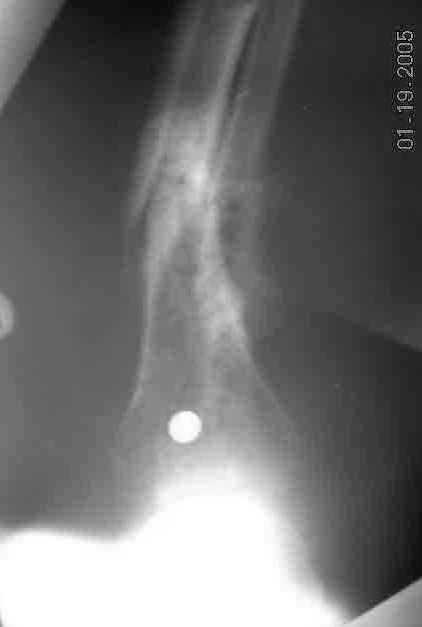

mal-non-union distal tibia in a diabetic |

Dear Group,Would like to present following case.68 yr old diabetic patient who sustained fractured distal tibia and fibula in distal third, treated with intramedullary rod. 4 weeks later, screws broke, sending tibial nail through distal tibia. Nail removed and external fixator applied. At time of ex-fix, blood supplyto foot noted to be nil. (Oxygen saturatioon of great toe 0%). Patient then underwent arterial bypass surgery which has restored blood supply. Ex-fix removed at 5 months with what appeared to be healing. Patient was then allowed to walk on the leg. He returns one month after weight bearing allowed with accomnpanying x-rays. My plan was to open non-union site, curette out fibrous tissue, bone graft and apply ex-fix (Ilizarov Type). Question: Would anyone opt for a repeat im nailing after opening and curretage and bone grafting?Thanks in advance,Louis D. Nunez, MDFishkill, NY

Why not closed nailing only, without any site opening? I would use 12 mm (so minimal reaming) closed section titanium nail with all locking options in the distal fragment, statically locked for 2-3 month. If site mobility now is not loose, it makes sense to apply ex-fix for gradual alignment before. PerQ osteotomy of the fibula if needed (presented x-rays don't show whether it is healed). The nail becomes shaft endoprosthesis so the leg immediately must be fully loadable regardless bony union.